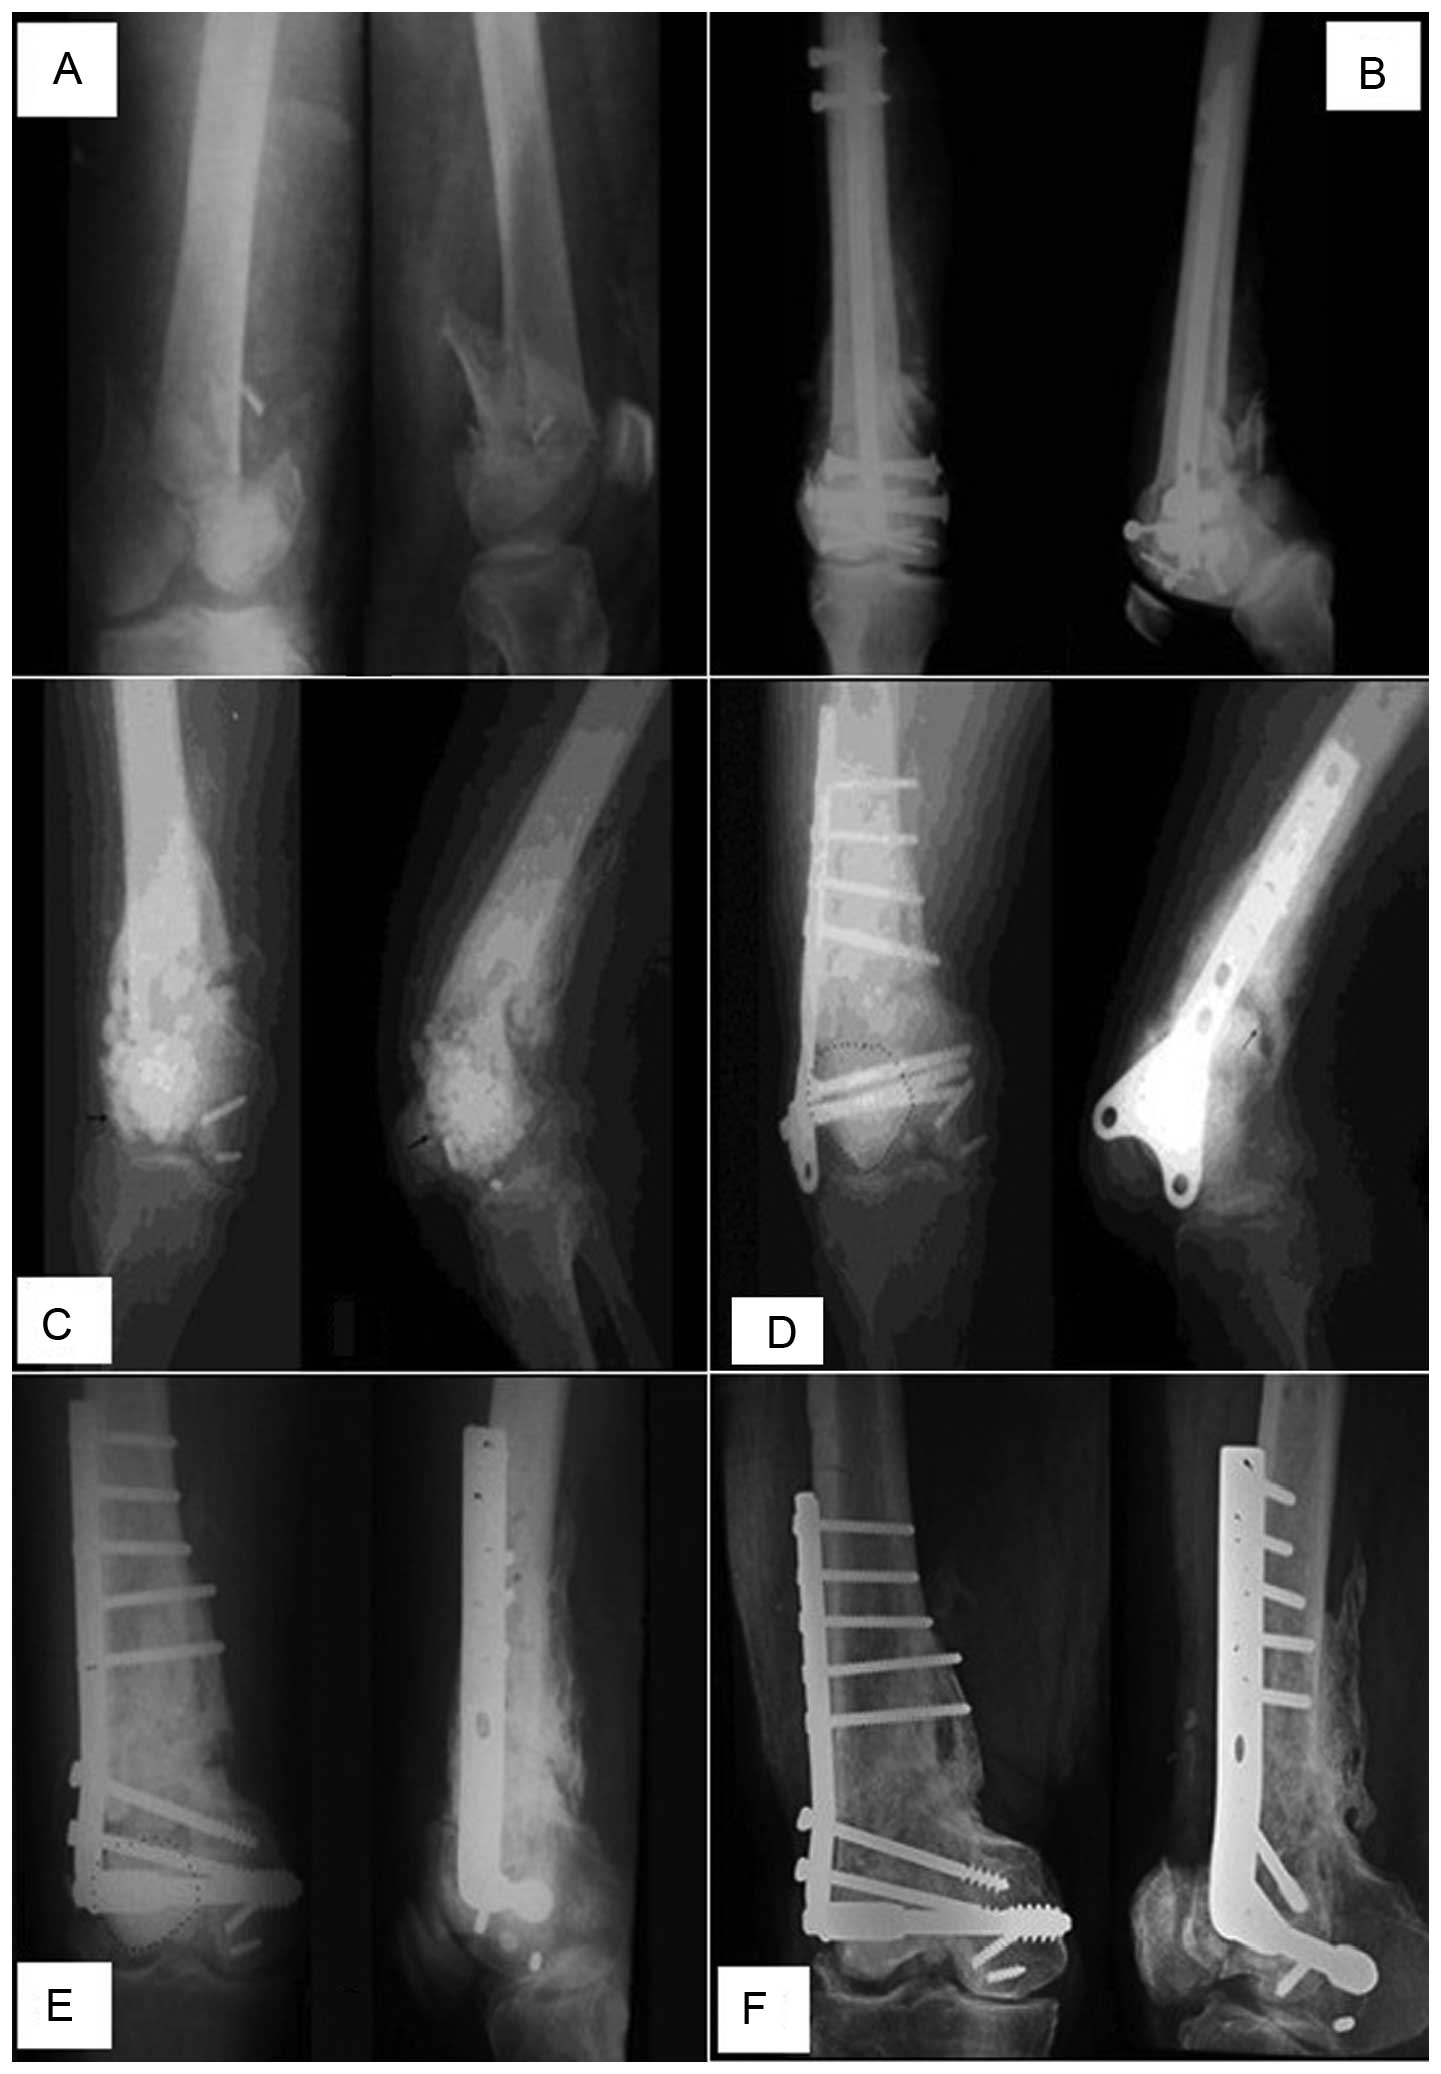

Combined debridement, bone graft and articular cavity sealing using synovium in treating metaphyseal osteomyelitis involving knee joints

The aim of this study was to investigate the efficacy of combined debridement, bone graft and articular cavity sealing using synovium in the treatment of metaphyseal osteomyelitis involving the knee joint. Eleven patients with metaphyseal osteomyelitis, which involved femurs in 4 patients and tibiae in 7, were included. The patients received a novel treatment, which combined debridement, bone graft and articular cavity sealing using the synovium. Of the 11 patients, 4 patients with knee joint instability received a structural allograft and 7 with a stable knee joint underwent a particulate bone graft. The 11 patients underwent regular clinical and radiological evaluation; the average follow-up was 74 months (range, 58-96). Infection recurrence in the joint and bone graft area was not observed in 10 of the 11 cases. In one patient, who underwent a lateral granular cancellous bone allograft in the right tibial plateau, the infection recurred 2 weeks later in the graft area. The infection was arrested 3 months after re-debridement and a bilateral ilium bone graft to eliminate the dead space. Combined debridement, bone graft and articular cavity sealing using the synovium may be a feasible treatment for metaphyseal osteomyelitis involving the knee joint.